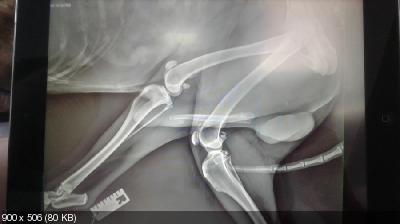

Пес обследован врачем.

Кровь ОАК и Биохимия в пределах показателей, сердце и легкие послушали в норме, по рентгену - задние лапы без изменений, передние - запущенный артроз плечевых суставов, в позвоночнике пуля, перелома по снимкам не обнаружено.

Когти начали врастать в подушечки-пострижены. Запущены зубы-гнилые и сильный запах, нужно будет лечить после курса обезболивающих и противоартрозных препаратов и соответствующее кормление.